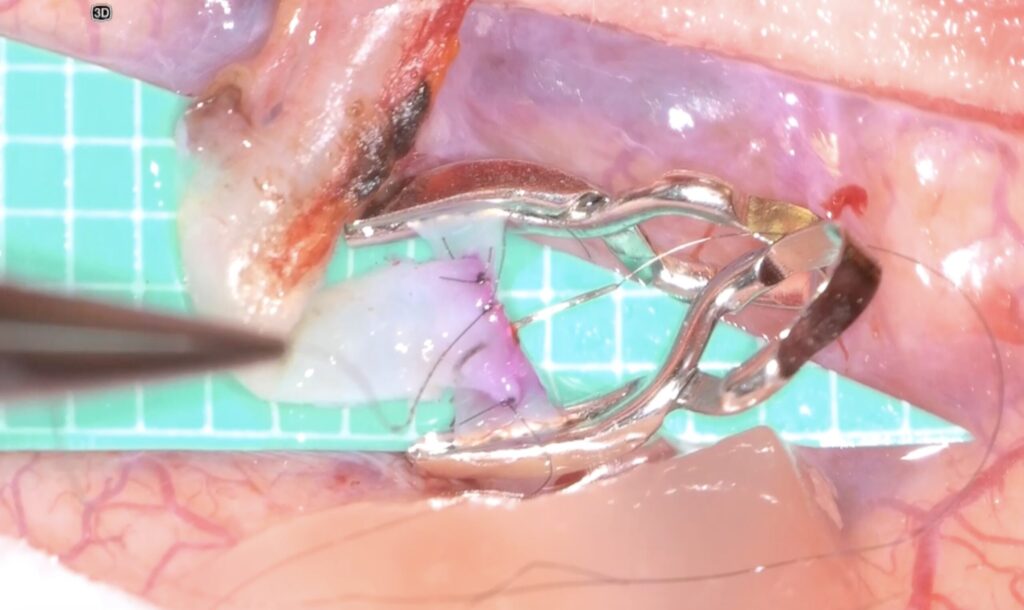

外視鏡を用いると吻合時にはデジタルズームをフットスイッチで入れると瞬時に高拡大にできます。

糸が通ったら、また瞬時にデジタルズームを切ります。

そして糸を結びます

次の針はまち針のように通してあり、しかも糸は常に繋がっていますので、針は無くなりません(Needle parking mehtod)